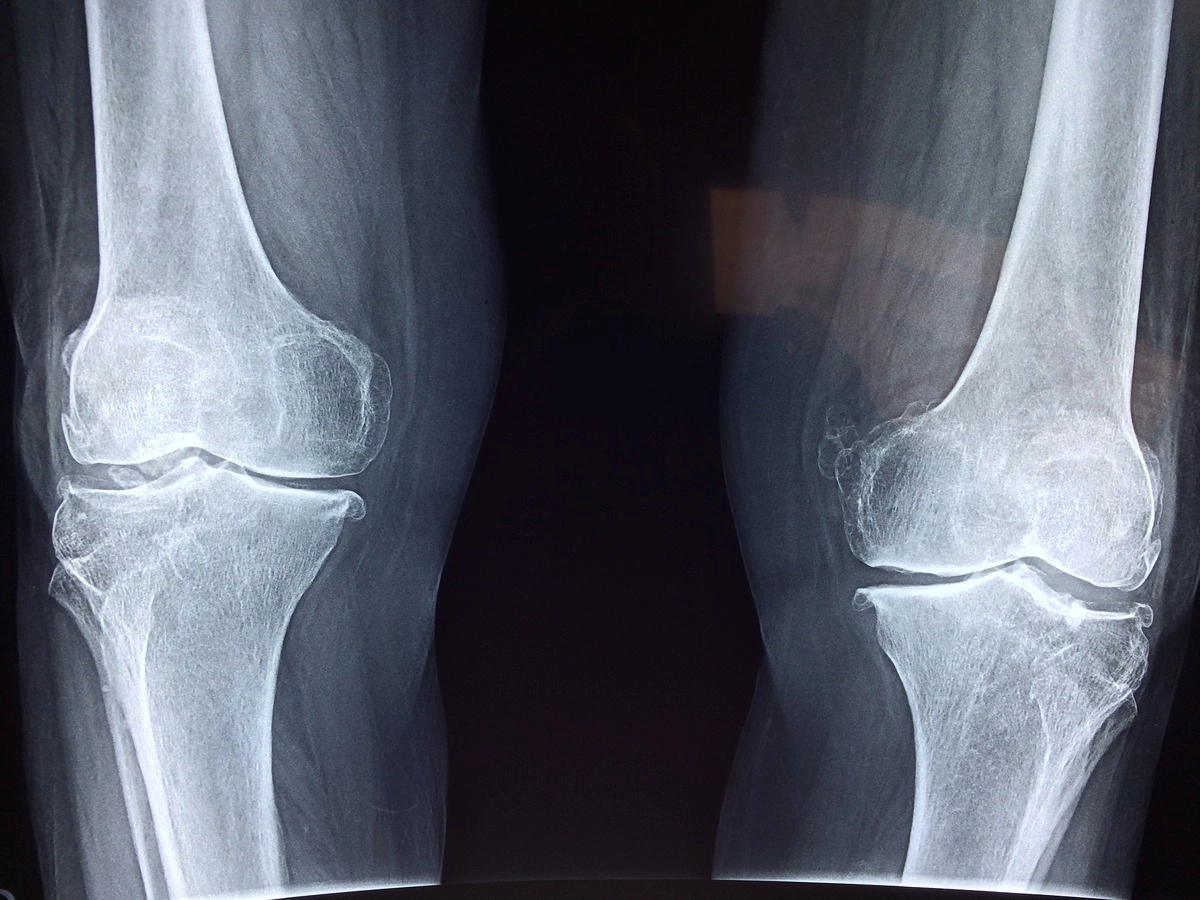

В работе ученых, опубликованной в Journal of Bone and Mineral Research, для изучения связей между здоровьем костей и сердечно-сосудистой системой использовалась комбинация рентгеновских снимков и биомаркеров крови большого количества людей, чьи данные хранятся в UK Biobank (масштабная база данных для исследований в области здравоохранения).

Исследователи обнаружили, что более низкая плотность костной ткани была связана с большей жесткостью артерий (что указывает на плохое состояние сердечно-сосудистой системы) как у мужчин, так и у женщин. Также ученые выяснили, что люди с остеопорозом имеют повышенный риск смерти от ишемической болезни сердца, а механизмы, лежащие в основе взаимосвязи костей и сердца у женщин и мужчин различаются.